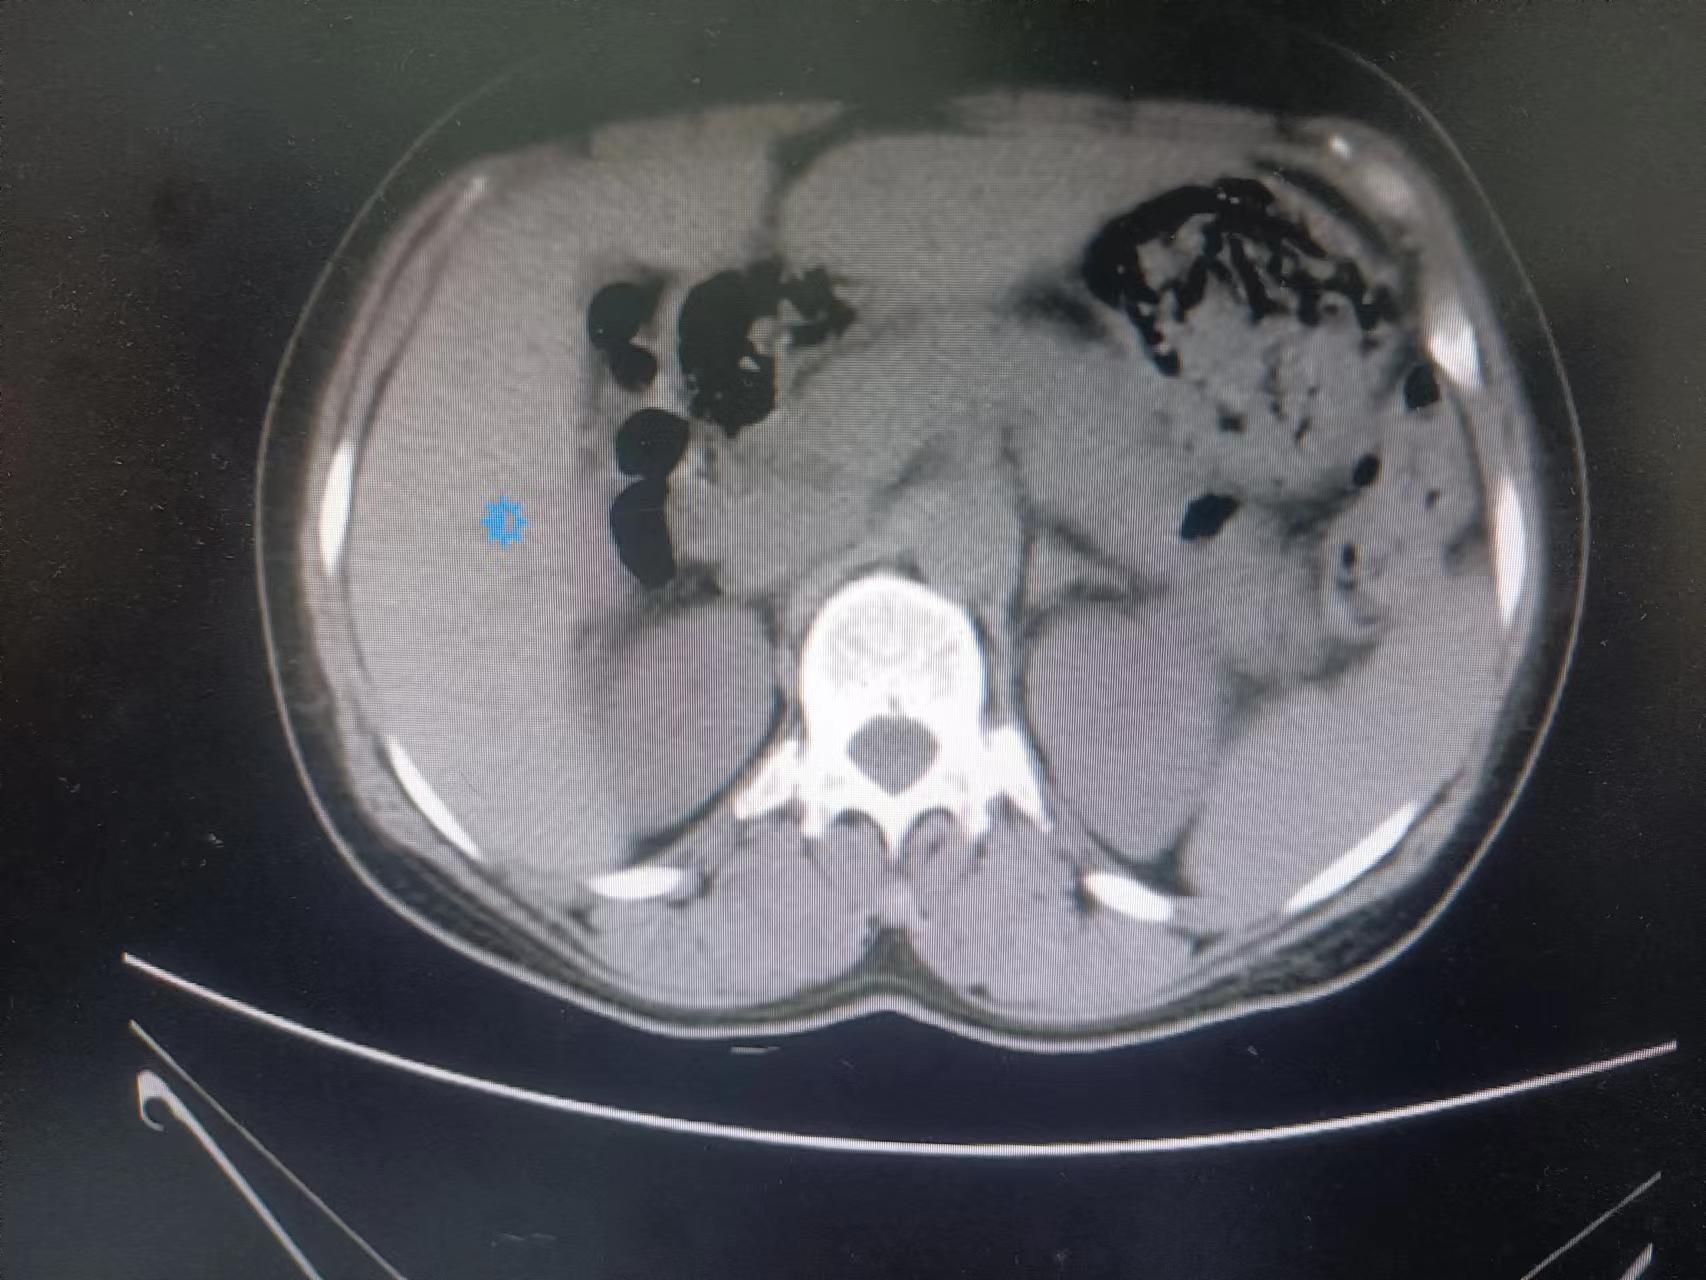

术后复查结果显示结石已基本排除干净,李爷爷恢复良好,为表达感谢,特将一面锦旗送至泌尿外科。

术后